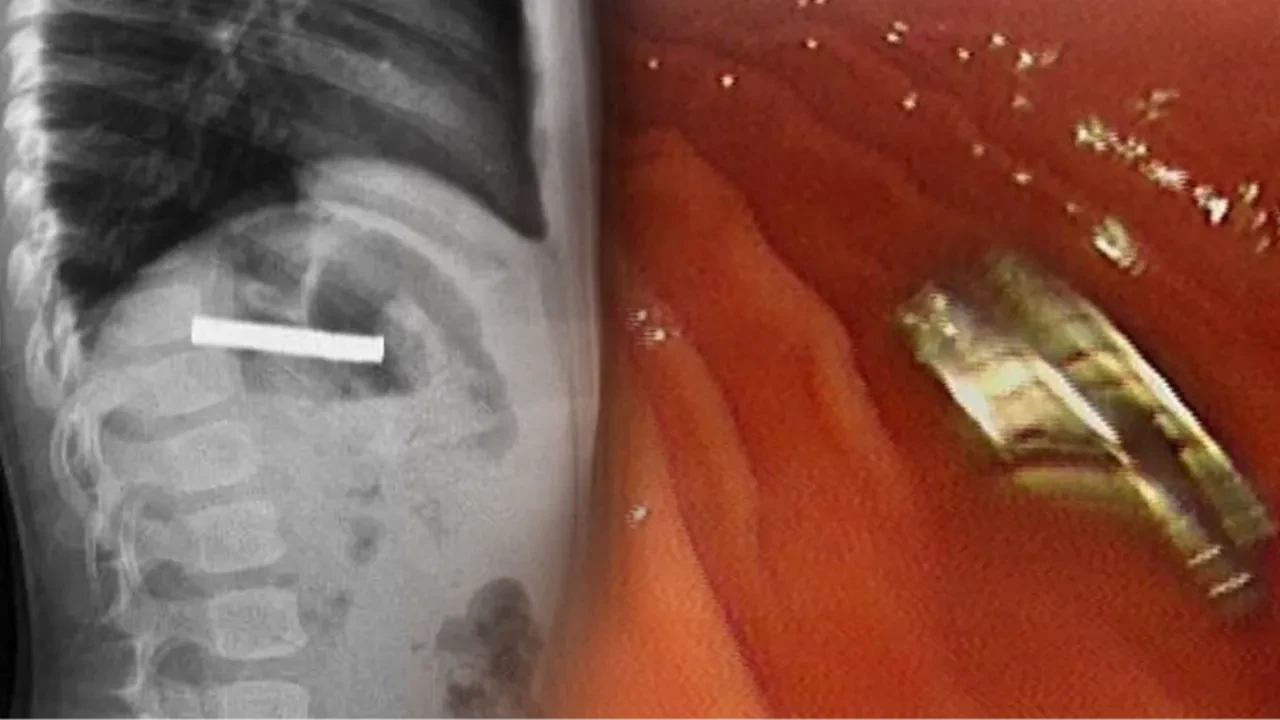

Erzurum’da 3 yaşındaki çocuğun rahatsızlanması sonrası aile hemen hastaneye başvurdu. Erzurum'dan Erzincan'a sevk edilen çocuğun boğazında yabancı cisimler tespit edildi.

Fırat Üniversitesi Çocuk Gastroenteroloji Hepatoloji ve Beslenme Bilim Dalı Başkanı Prof. Dr. Yaşar Doğan, çocuk hastanın yemek borusuna yapışmış 19 mıknatısı endoskopik yöntemle çıkardı. Mıknatıslar uzun süre yemek borusunda takılı kaldığı için yemek borusu ve mide girişinde zedelenmeler olurken, çocuğun sağlık durumunun iyi olduğu ve taburcu edildiği öğrenildi.